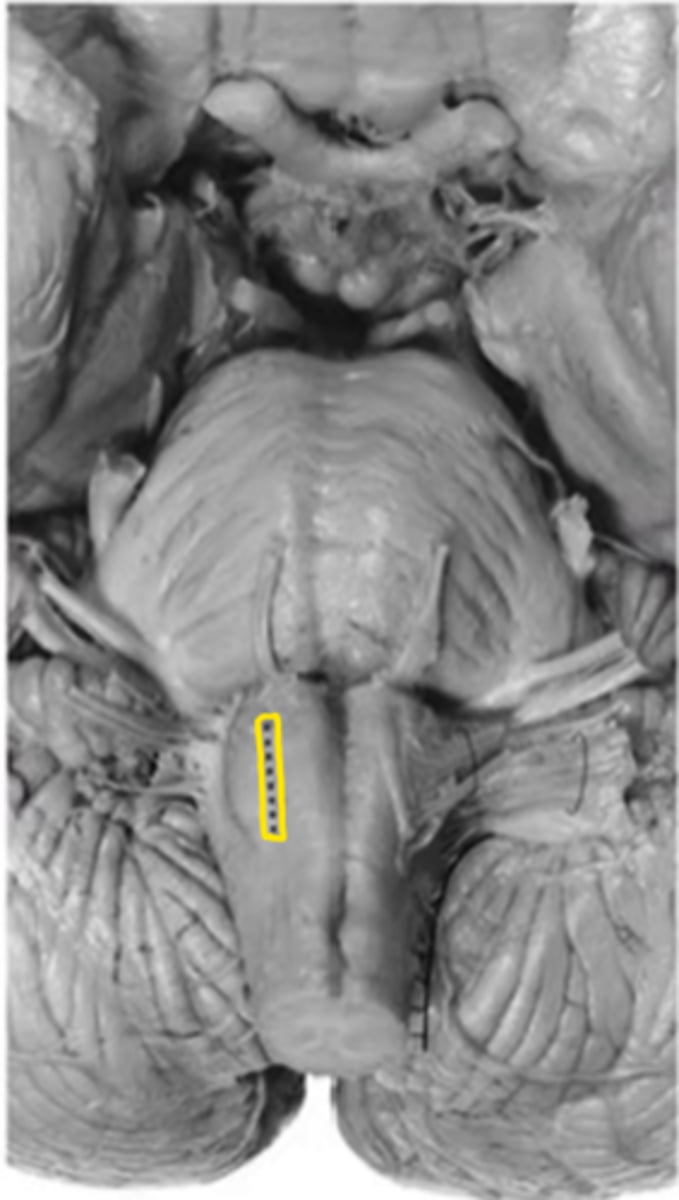

medullary pyramids

ID the structure

anterior median sulcus

olive